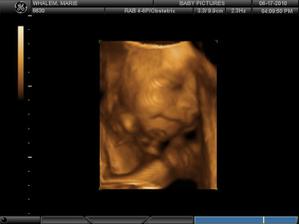

• 12.2.2010 Nas druhy ultrazvuk v 11. tydnu nam ukazal velmi aktivni miminko hybajici ruckama a nozkama.

• 30.3. 2010 dalsi ultrazvuk v druhem trimestru odhalil zdrave miminko - je to chlapecek 🙂